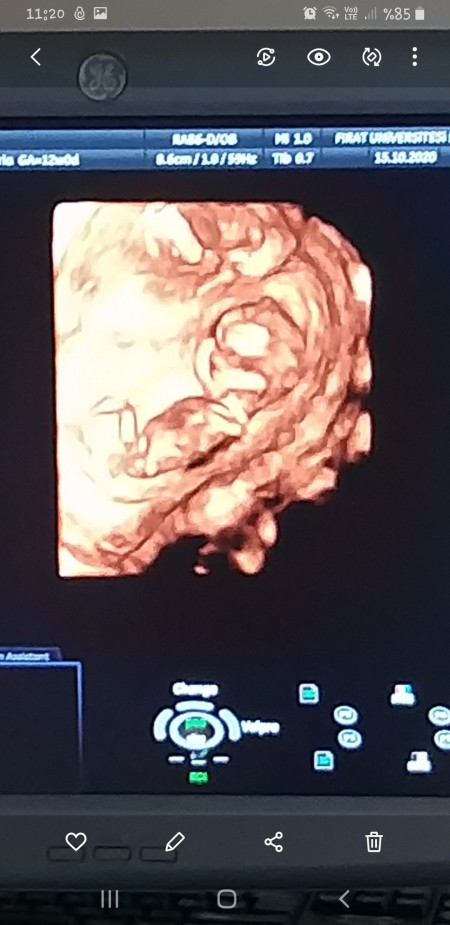

cinsiyet tahmini olan var mi 17 haftalik olacam ama hala belli degil bu goruntu ikizlerimden birinin goruntusu cift yumurta ikizlerim olacak :)

bi kiz bi erkek olabilir demisti doktorum ama 12. haftada soylemisti bunu

doktorm 12.haftada bi kiz bi erkek gibi dedi ama sadece bi ihtimal kesin konusmamisti :)